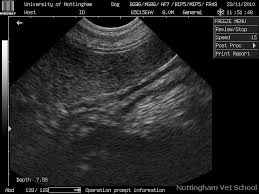

Black Spot On Kidney X Ray. X ray abdomen is simple cost effective and better choice to diagnose. A spot is not a standard descriptor it doesn t really mean anything from a radiology standpoint.

By cathey newton134465 4 posts last post over a year ago. Yesterday was my xray day because im having this back pain so they check if somethings wrong with my kidney. So im kind of worried still about that.

My doctor told me that my kidneys were ok but he was wondering about that black stuff. What might it be. By cathey newton134465 4 posts last post over a year ago. Rapid muscle tone loss.